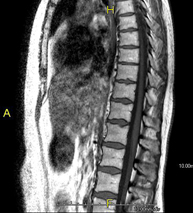

Prova diagnòstica no invasiva que consisteix en l'obtenció d'imatges d'alta definició anatòmica de la columna cervical mitjançant l'ús d'un camp electromagnètic i ones de ràdio (com un emissor i un receptor). No utilitza radiació ionitzant. Indicacions: traumatisme, degeneració de la columna, hèrnies. - RM de columna dorsal

Prova diagnòstica no invasiva que consisteix en l'obtenció d'imatges d'alta definició anatòmica de la columna dorsal mitjançant l'ús d'un camp electromagnètic i ones de ràdio (com un emissor i un receptor). No utilitza radiació ionitzant. Indicacions: traumatisme, problemes degeneratius, hèrnies, tumors. - RM de Columna lumbar

Prova diagnòstica no invasiva que consisteix en l'obtenció d'imatges d'alta definició anatòmica de la columna lumbar i sacre mitjançant l'ús d'un camp electromagnètic i ones de ràdio (amb un emissor i un receptor). No utilitza radiació ionitzant. Indicacions: traumatismes, ciàtica, hèrnies discals, tumors, infeccions - RM Mielografia

Prueba diagnóstica no invasiva que consiste en la obtención de imágenes de alta definición anatómica de la columna cervical mediante el empleo de un campo electromagnético y ondas de radio (con un emisor y un receptor). No utiliza radiación ionizante. Indicaciones: traumatismo, degeneración de la columna, hernias. - RM Columna Dorsal

Prueba diagnóstica no invasiva que consiste en la obtención de imágenes de alta definición anatómica de la columna dorsal mediante el empleo de un campo electromagnético y ondas de radio (con un emisor y un receptor). No utiliza radiación ionizante. Indicaciones: traumatismo, problemas degenerativos, hernias, tumores. - RM Columna Lumbar

Prueba diagnóstica no invasiva que consiste en la obtención de imágenes de alta definición anatómica de la lumbar y sacra mediante el empleo de un campo electromagnético y ondas de radio (con un emisor y un receptor). No utiliza radiación ionizante. Indicaciones: traumatismos, ciática, hernias discales, tumores, infecciones. - RM Sacro-cóccix